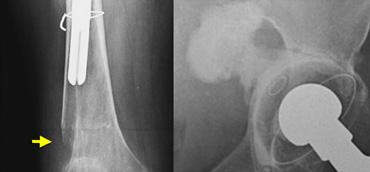

LEFT: Hybrid THA with cemented femoral stem and noncemented acetabular cup.RIGHT: Bone ingrowth arthroplasty. Density lateral to femoral stem in Gruens zone I is a bone graft.

Thay khớp háng toàn phần lai là sự kết hợp giữa cố định có xi măng và không xi măng.

Do các thành phần ổ cối có xi măng có xu hướng bị lỏng theo thời gian, đôi khi người ta sử dụng kết hợp thành phần ổ cối không xi măng với thành phần xương đùi có xi măng.

Nhìn chung, có xu hướng ưu tiên sử dụng thay khớp háng toàn phần không xi măng, vì cho kết quả lâu dài tốt hơn.

Bên trái chúng ta thấy một khớp háng nhân tạo toàn phần (THA) lai ghép với cốc ổ cối tích hợp xương và thân xương đùi gắn xi măng, và bên cạnh đó là một khớp háng nhân tạo toàn phần không xi măng tích hợp xương.

Gãy xương quanh khớp nhân tạo

Gãy xương có thể xảy ra sau phẫu thuật ở những bệnh nhân có chất lượng xương kém và sử dụng khớp nhân tạo thay thế có cán dài, hoặc khi giải phẫu bất thường như trong trường hợp loạn sản khớp háng hoặc đã từng phẫu thuật trước đó.

Gãy xương cũng phổ biến hơn với các cán xương đùi không xi măng, vì các loại này phải vừa khít chính xác và có thể gây gãy xương trong quá trình đặt khớp.

Tỷ lệ gãy xương dao động từ 0,1 đến 1,0 phần trăm đối với các thành phần có xi măng và từ 3 đến 18 phần trăm đối với các thành phần không xi măng. Hầu hết các trường hợp gãy xương trong phẫu thuật xảy ra ở phía xương đùi.